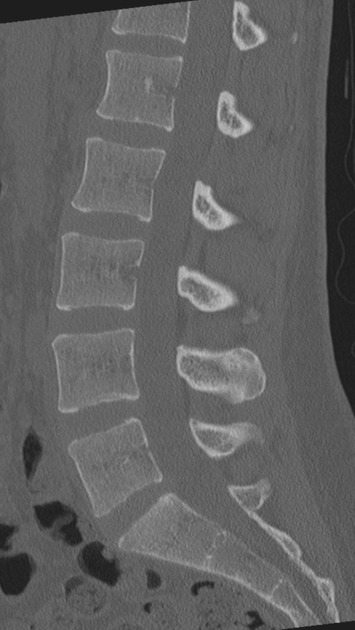

A CT Spine With Contrast (Contrast-Enhanced Computed Tomography) is a specialized diagnostic imaging scan that provides high-resolution images of the spine, including vertebrae, discs, spinal cord, and surrounding tissues. The contrast dye used in this scan increases the clarity while viewing the blood vessels and soft tissues, allowing for a more accurate check of spinal conditions. The CT Spine With Contrast is often done to detect fractures, disc herniations, bone tumors, or spinal infections, especially when standard X-rays or MRIs are insufficient. This low-risk and very effective procedure is done in hospitals or diagnostic centres, and the CT Spine report is generally available within a few hours, aiding doctors in making accurate diagnoses.